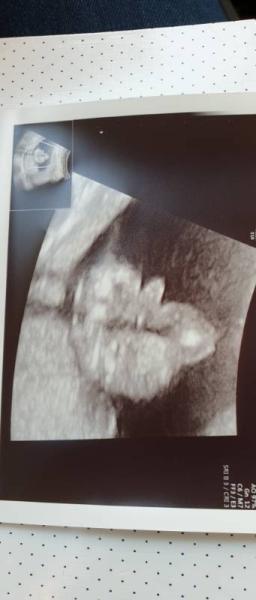

Ich denke Team Mein Frauenarzt sagte oh müssen wir garnicht lang schauen da ist er

Bild zu Outing - Forum für März - Mamis

Das sieht doch sehr eindeutig aus.